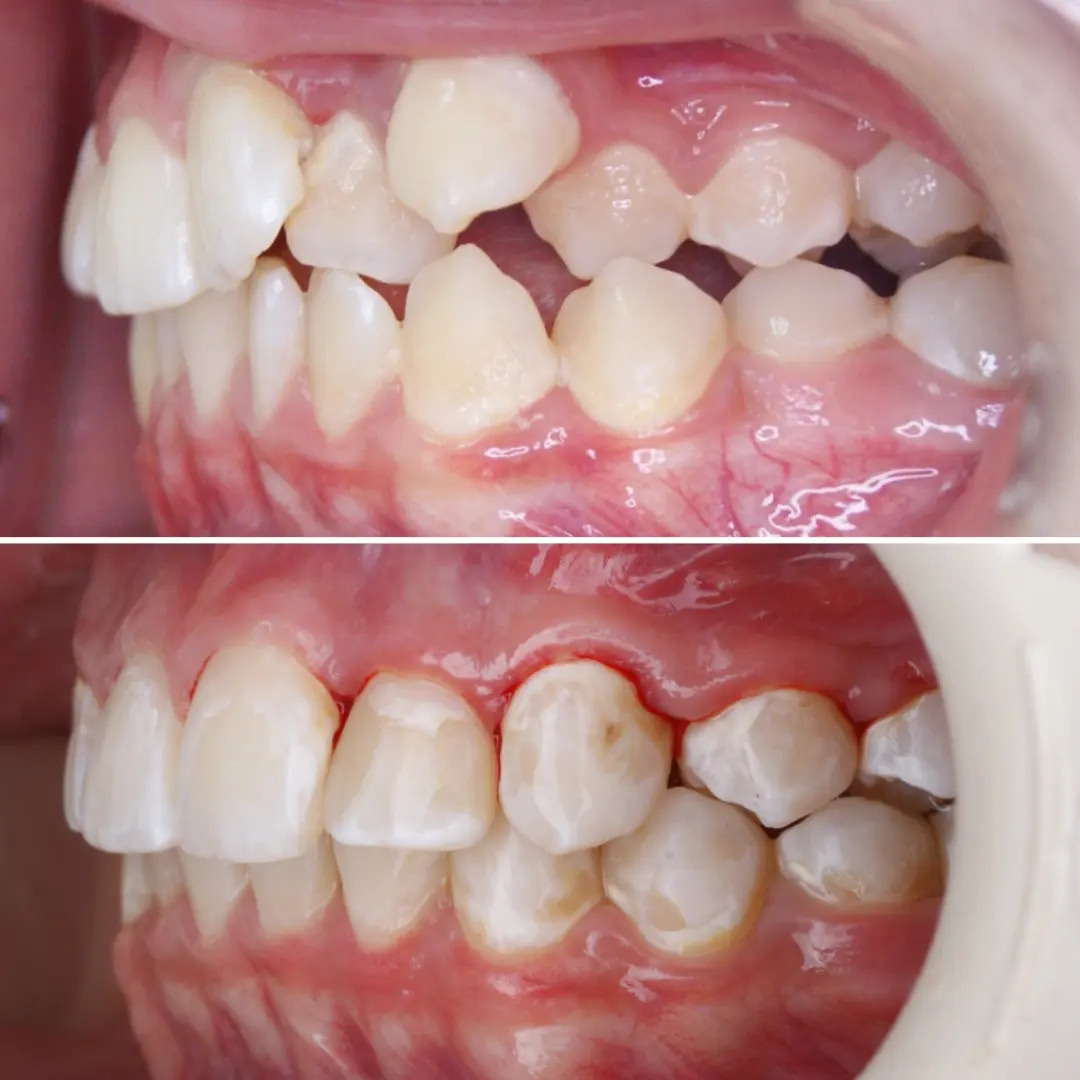

Большое путешествие зубов на своё законное место.

Эта фраза знакома многим ответственным родителям, которые привели на приём к ОРТОДОНТУ своего ребёнка в 5-10 лет, заподозрив проблему или понимая, что места постоянным зубам откровенно не хватает! Горькая правда в том, что брекеты - не волшебное средство от всех проблем, они "расставляют" зубы внутри сформированого объёма челюсти, но никак не влияют на её рост. Родители ждут, а тем временем драгоценное время, когда ребёнок растёт, уходит... Во взрослом возрасте приходится удалять здоровые зубы или прибегать к ортогнатической хирургической операции. 📸 На фото узкая нижняя челюсть, места постоянным зубам нет, боковые резцы прорезываются "вторым рядом".

❓Ну что? Будем ждать 12 лет? Или будем помогать ребёнку?

✅ Помогаем с помощью расширяющей дуги, пружины и зацепных элементов, которые зафиксированы на МОЛОЧНЫЕ зубы